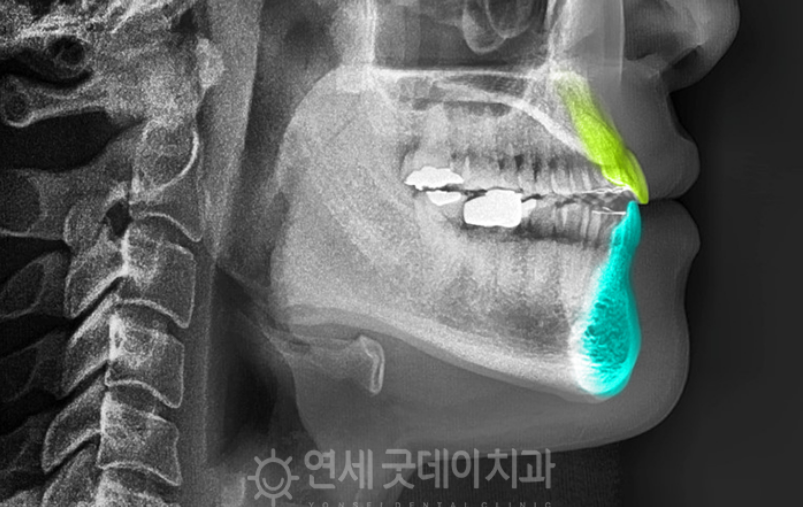

하지만 엑스레이 촬영을 통해 내부를 자세히

들여다 보면 이상증세를 확인할 수 있었습니다.

위 사진과 같이 엑스레이로 측면을 촬영하게 되면

위 치아가 아래치아보다 안으로 말려들어간 형상을

볼 수 있습니다.

이는 정상적인 교합과 달리 거꾸로 물리는

‘반대교합’ 양상을 확인할 수 있습니다.

작은 어금니는 작은어금니끼리, 송곳니는

송곳니끼리, 맞물리는 것이 정상이지만,

아래 치아가 앞으로 나와있어 한 칸씩 밀려있는

상태를 확인할 수 있습니다.